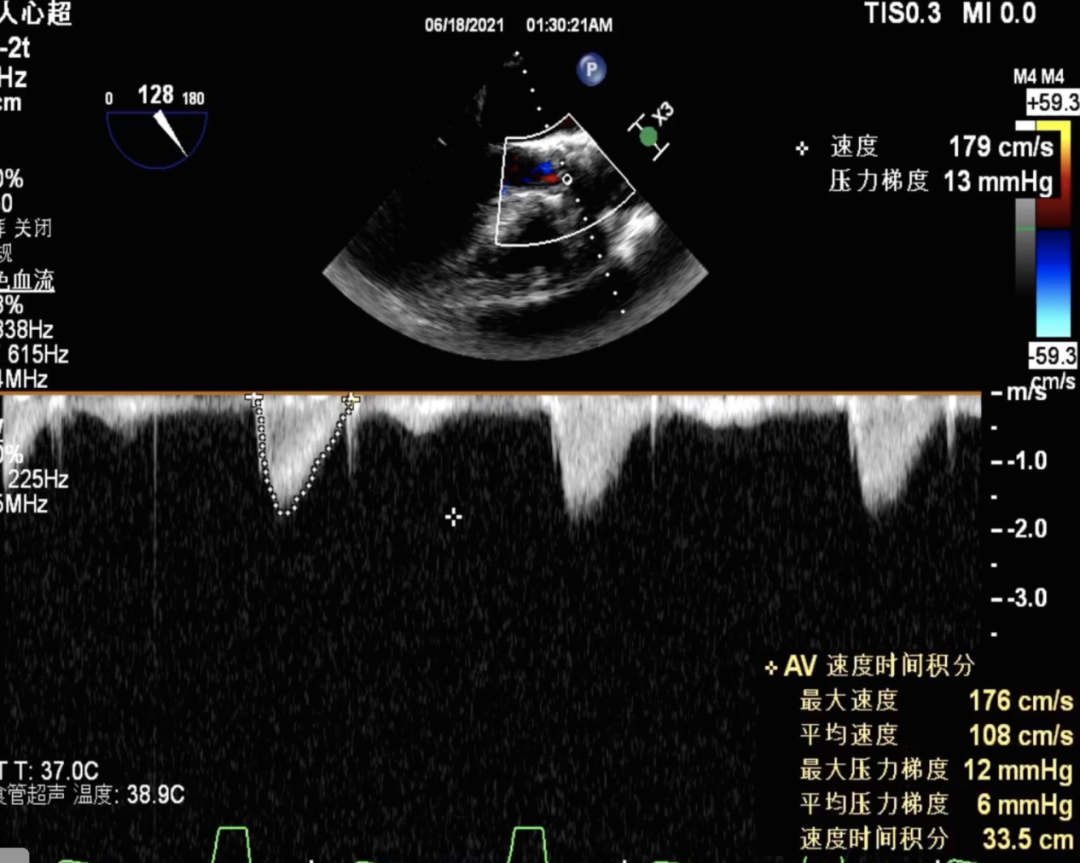

患者:老年女性,因劳累性呼吸困难收治入院,超声心动图显示主动脉瓣增厚,回声增强,开放受限。平均跨瓣压差 41mmHg,瓣上速度 4.5s/m,瓣口面积0.8cm²,提示主动脉瓣重度狭窄并伴有轻度关闭不全。

主动脉根部造影提示瓦氏窦整体形态偏小,决定给予冠脉保护

18mm球囊预扩,无明显腰征,少许瓣周漏,未见冠脉阻挡,决定选择TaurusOne®AV23瓣膜。

瓣膜释放后形态位置良好,造影无返流

术后即刻评估: